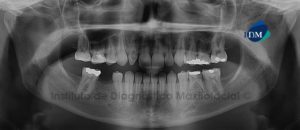

041 – Planificación y Tratamiento en Rehabilitación Oral con Prótesis sobre Implantes usando Análisis Cefalométrico

En los pacientes desdentados, que requieren una prótesis completa ya sea convencional o implanto soportada, los dientes artificiales se colocan en la prótesis completa por